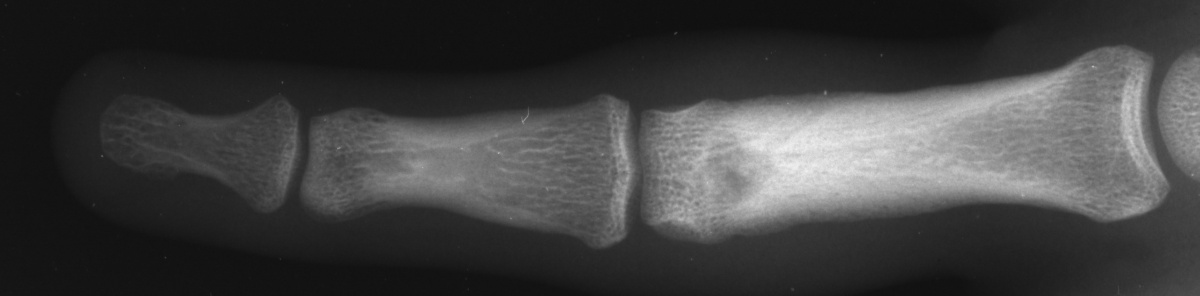

| Case 1. This 18 year old man

presented with a two year history of pain and swelling of the distal

aspect of his proximal phalanx. |

| Plain films showed

sclerosis within a radiolucent area and adjacent cortical/endosteal

sclerosis. |

| The tumor was removed with

a burr. |

| Despite extensive

resection, over three quarters of the cortical circumference remained,

and structural reinforcement was not necessary. |

| The defect was packed with

cancellous bone harvested from the dorsal distal radius. |